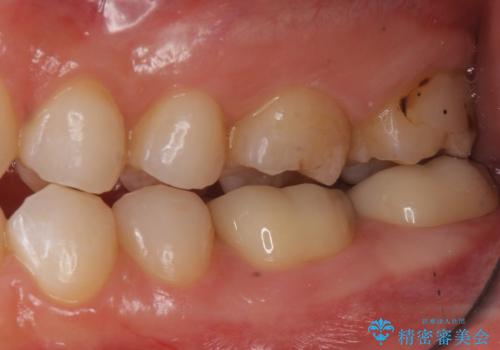

変色した樹脂の詰め物 セラミックでのやり替え

奥歯が樹脂の詰め物で継ぎ接ぎになっていることが確認されたため、今後の虫歯リスクを減らすために適合の良いフルジルコニアクラウンを入れていきます。

- 左下67 仮歯+フルジルコニアクラウン 22,000円+154,000円費用は治療当時の料金となります

樹脂で継ぎ接ぎになった歯はそうでない歯と比べて虫歯になるリスクが高いです。

樹脂をすべて取り、虫歯も取り切った後に適合の良いクラウンを装着することで今後の虫歯リスクを減らすことができます。